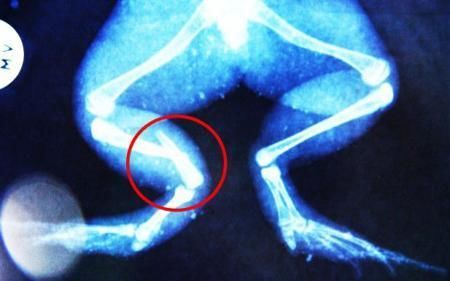

环球网4月2日报道 据《每日邮报》报道,上个月,南非大牛蛙布鲁莱的右小腿被邻居家的一只狗咬到,导致粉碎性骨折,现在经过2个小时的手术,它的断腿已经被接上,它也因此成为有史以来第一只通过外科手术用钢针接上断腿的青蛙。

布鲁莱的主人,居住在南非约翰内斯堡附近的62岁的安妮·米恩斯说:“我对这只青蛙如此关心,人们一定认为我疯了,但是我无法眼睁睁看着它那么痛苦。青蛙因其灵活的腿脚而著称,一想到布鲁莱的腿里要留下一个薄金属片,我就感到心痛。然而我知道,如果不进行手术,布鲁莱以后就没办法动弹了。因此我匆匆赶到兽医那里,央求他给这只可怜的青蛙动手术。这位兽医整天救助小猫小狗,他很难理解为什么我这么担心一只青蛙,但是最终他还是答应了给布鲁莱做手术。手术后是几个小时的焦急等待,我们希望它能快快苏醒过来。不过现在它的伤口已经愈合,又能在花园里跳来跳去了。X光照射显示,它会恢复的跟以前一样。”

野生生物专家安妮经常为学校写教材,她认为这是人类第一次通过手术给一只青蛙接断腿。在手术开始阶段,兽医把少量给狗用的麻醉药注入到这只青蛙体内,让它失去知觉。然后他在布鲁莱的断腿上切开一个小口,把一根小钢针植入腿里。最后兽医给它缝了9针,把切口缝合在一起。仅仅几周后,布鲁莱就能在安妮家附近活动了。这只青蛙大约已有25岁,主要以啮齿动物、蛇和其他青蛙为食。布鲁莱所属的牛蛙种群正在不断减小,目前只能在非洲南部的湿地里才能看到这种青蛙。